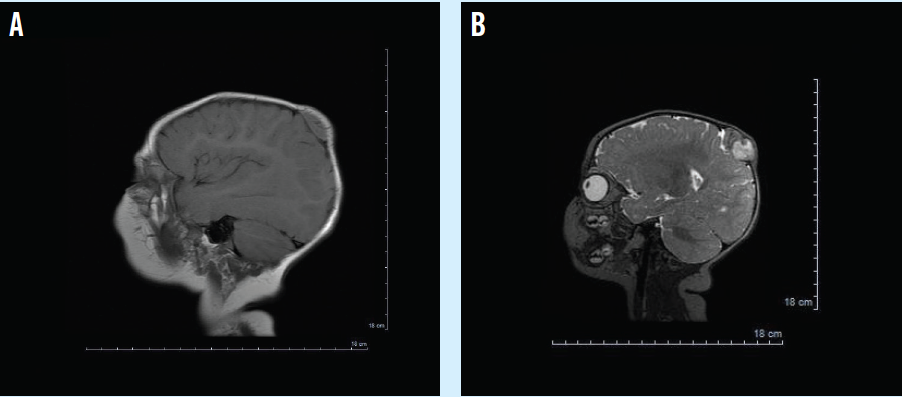

At 6 months old, the infant was developing normally without any localizing neurological symptoms. On physical examination, he had a soft, nontender mass in the parietal-occipital region measuring about 2.0 × 2.5 cm with well-defined borders. Ultrasound of the head showed an echogenic well-defined mass with high vascularity that appeared to be extra-axial, causing mass effect on the brain. Follow-up magnetic resonance imaging (MRI) of the head showed large intensely enhancing 2.7 × 3.5 × 2.5-cm extra-axial heterogeneous mass centered along the right paramedian posterior parietal bone (Figure).

He had a craniotomy for resection of supratentorial tumor and biopsy of the mass. The tumor was in between dural leaflets with adherence to adjacent draining veins and the superior sagittal sinus.